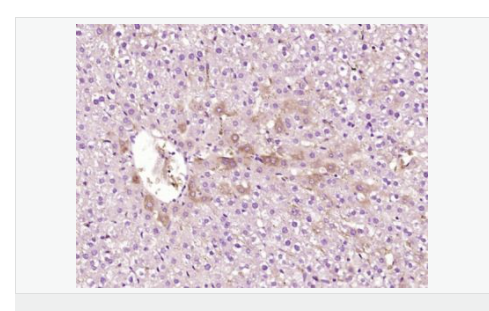

IHC-P,

| 产品应用 | WB=1:500-2000 ELISA=1:5000-10000 IHC-P=1:100-500 IHC-F=1:100-500 IF=1:100-500 (石蜡切片需做抗原修复) not yet tested in other applications. optimal dilutions/concentrations should be determined by the end user. |

| 产品介绍 | ATP7b is an important protein for copper transport and elimination of excess copper from the body. ATP7b transports metals in and out of cells using ATP. There are 3 known isoforms of the ATP7b gene; A is found in the liver, kidney, and brain, the shorter form B is found in brain tissue, and the third isoform, known as WND/140 KDA is found in mitochondria. Mutations in the ATP7b gene can cause Wilson's disease, an inherited disorder causing copper poisoning in the brain and liver. Function: Involved in the export of copper out of the cells, such as the efflux of hepatic copper into the bile. Subunit: Monomer. Interacts with COMMD1/MURR1. Subcellular Location: Golgi apparatus, trans-Golgi network membrane; Multi-pass membrane protein. Isoform 2: Cytoplasm. WND/140 kDa: Mitochondrion. Tissue Specificity: Most abundant in liver and kidney and also found in brain. Isoform 2 is expressed in brain but not in liver. The cleaved form WND/140 kDa is found in liver cell lines and other tissues. Post-translational modifications: Isoform 1 may be proteolytically cleaved at the N-terminus to produce the WND/140 kDa form. DISEASE: Defects in ATP7B are the cause of Wilson disease (WD) [MIM:277900]. WD is an autosomal recessive disorder of copper metabolism in which copper cannot be incorporated into ceruloplasmin in liver, and cannot be excreted from the liver into the bile. Copper accumulates in the liver and subsequently in the brain and kidney. The disease is characterized by neurologic manifestations and signs of cirrhosis. Similarity: Belongs to the cation transport ATPase (P-type) (TC 3.A.3) family. Type IB subfamily. Contains 6 HMA domains. SWISS: P35670 Gene ID: 540 Database links: Entrez Gene: 540 Human Omim: 606882 Human SwissProt: P35670 Human Unigene: 492280 Human Important Note: This product as supplied is intended for research use only, not for use in human, therapeutic or diagnostic applications. 铜转运蛋白质β链是铜转运蛋白质家族中的一种,可调节细胞内铜离子水平的铜转运P型三磷酸腺苷酶,ATP7B是生物体内广泛存在的一种极为重要的细胞膜上的酶,它的功能主要是维持细胞内外的离子及渗透压平衡、跨膜电化学和细胞的能量代谢. |